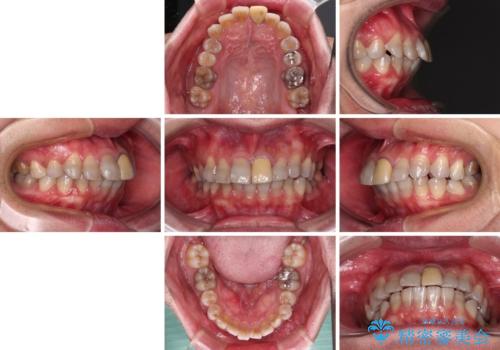

- 飛び出した前歯を気にして来院された患者様です。

口元を引っ込めるために上下左右の第一小臼歯4本を抜歯することとしました。

速やかに治療を進めたいとのことで、表側のワイヤー装置で矯正治療を行うこととしました。

特徴的な歯の色が気になっているとのことで、今後セラミッククラウンによる審美歯科治療を検討されているとのことで、矯正治療の後戻りが落ち着いたタイミングで治療を進めていく予定です。